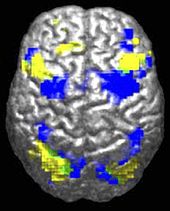

The underconnectivity theory of autism hypothesizes that autism is marked by underfunctioning high-level neural connections and synchronization, along with an excess of low-level processes.[93] Evidence for this theory has been found in functional neuroimaging studies on autistic individuals[37] and by a brainwave study that suggested that adults with ASD have local overconnectivity in the cortex and weak functional connections between the frontal lobe and the rest of the cortex.[94] Other evidence suggests the underconnectivity is mainly within each hemisphere of the cortex and that autism is a disorder of the association cortex.[95]

Research into causes has been hampered by the inability to identify biologically meaningful subgroups within the autistic population[127] and by the traditional boundaries between the disciplines of psychiatry, psychology, neurology and pediatrics.[128] Newer technologies such as fMRI and diffusion tensor imaging can help identify biologically relevant phenotypes (observable traits) that can be viewed on brain scans, to help further neurogenetic studies of autism;[129] one example is lowered activity in the fusiform face area of the brain, which is associated with impaired perception of people versus objects.[9] It has been proposed to classify autism using genetics as well as behavior.[130]